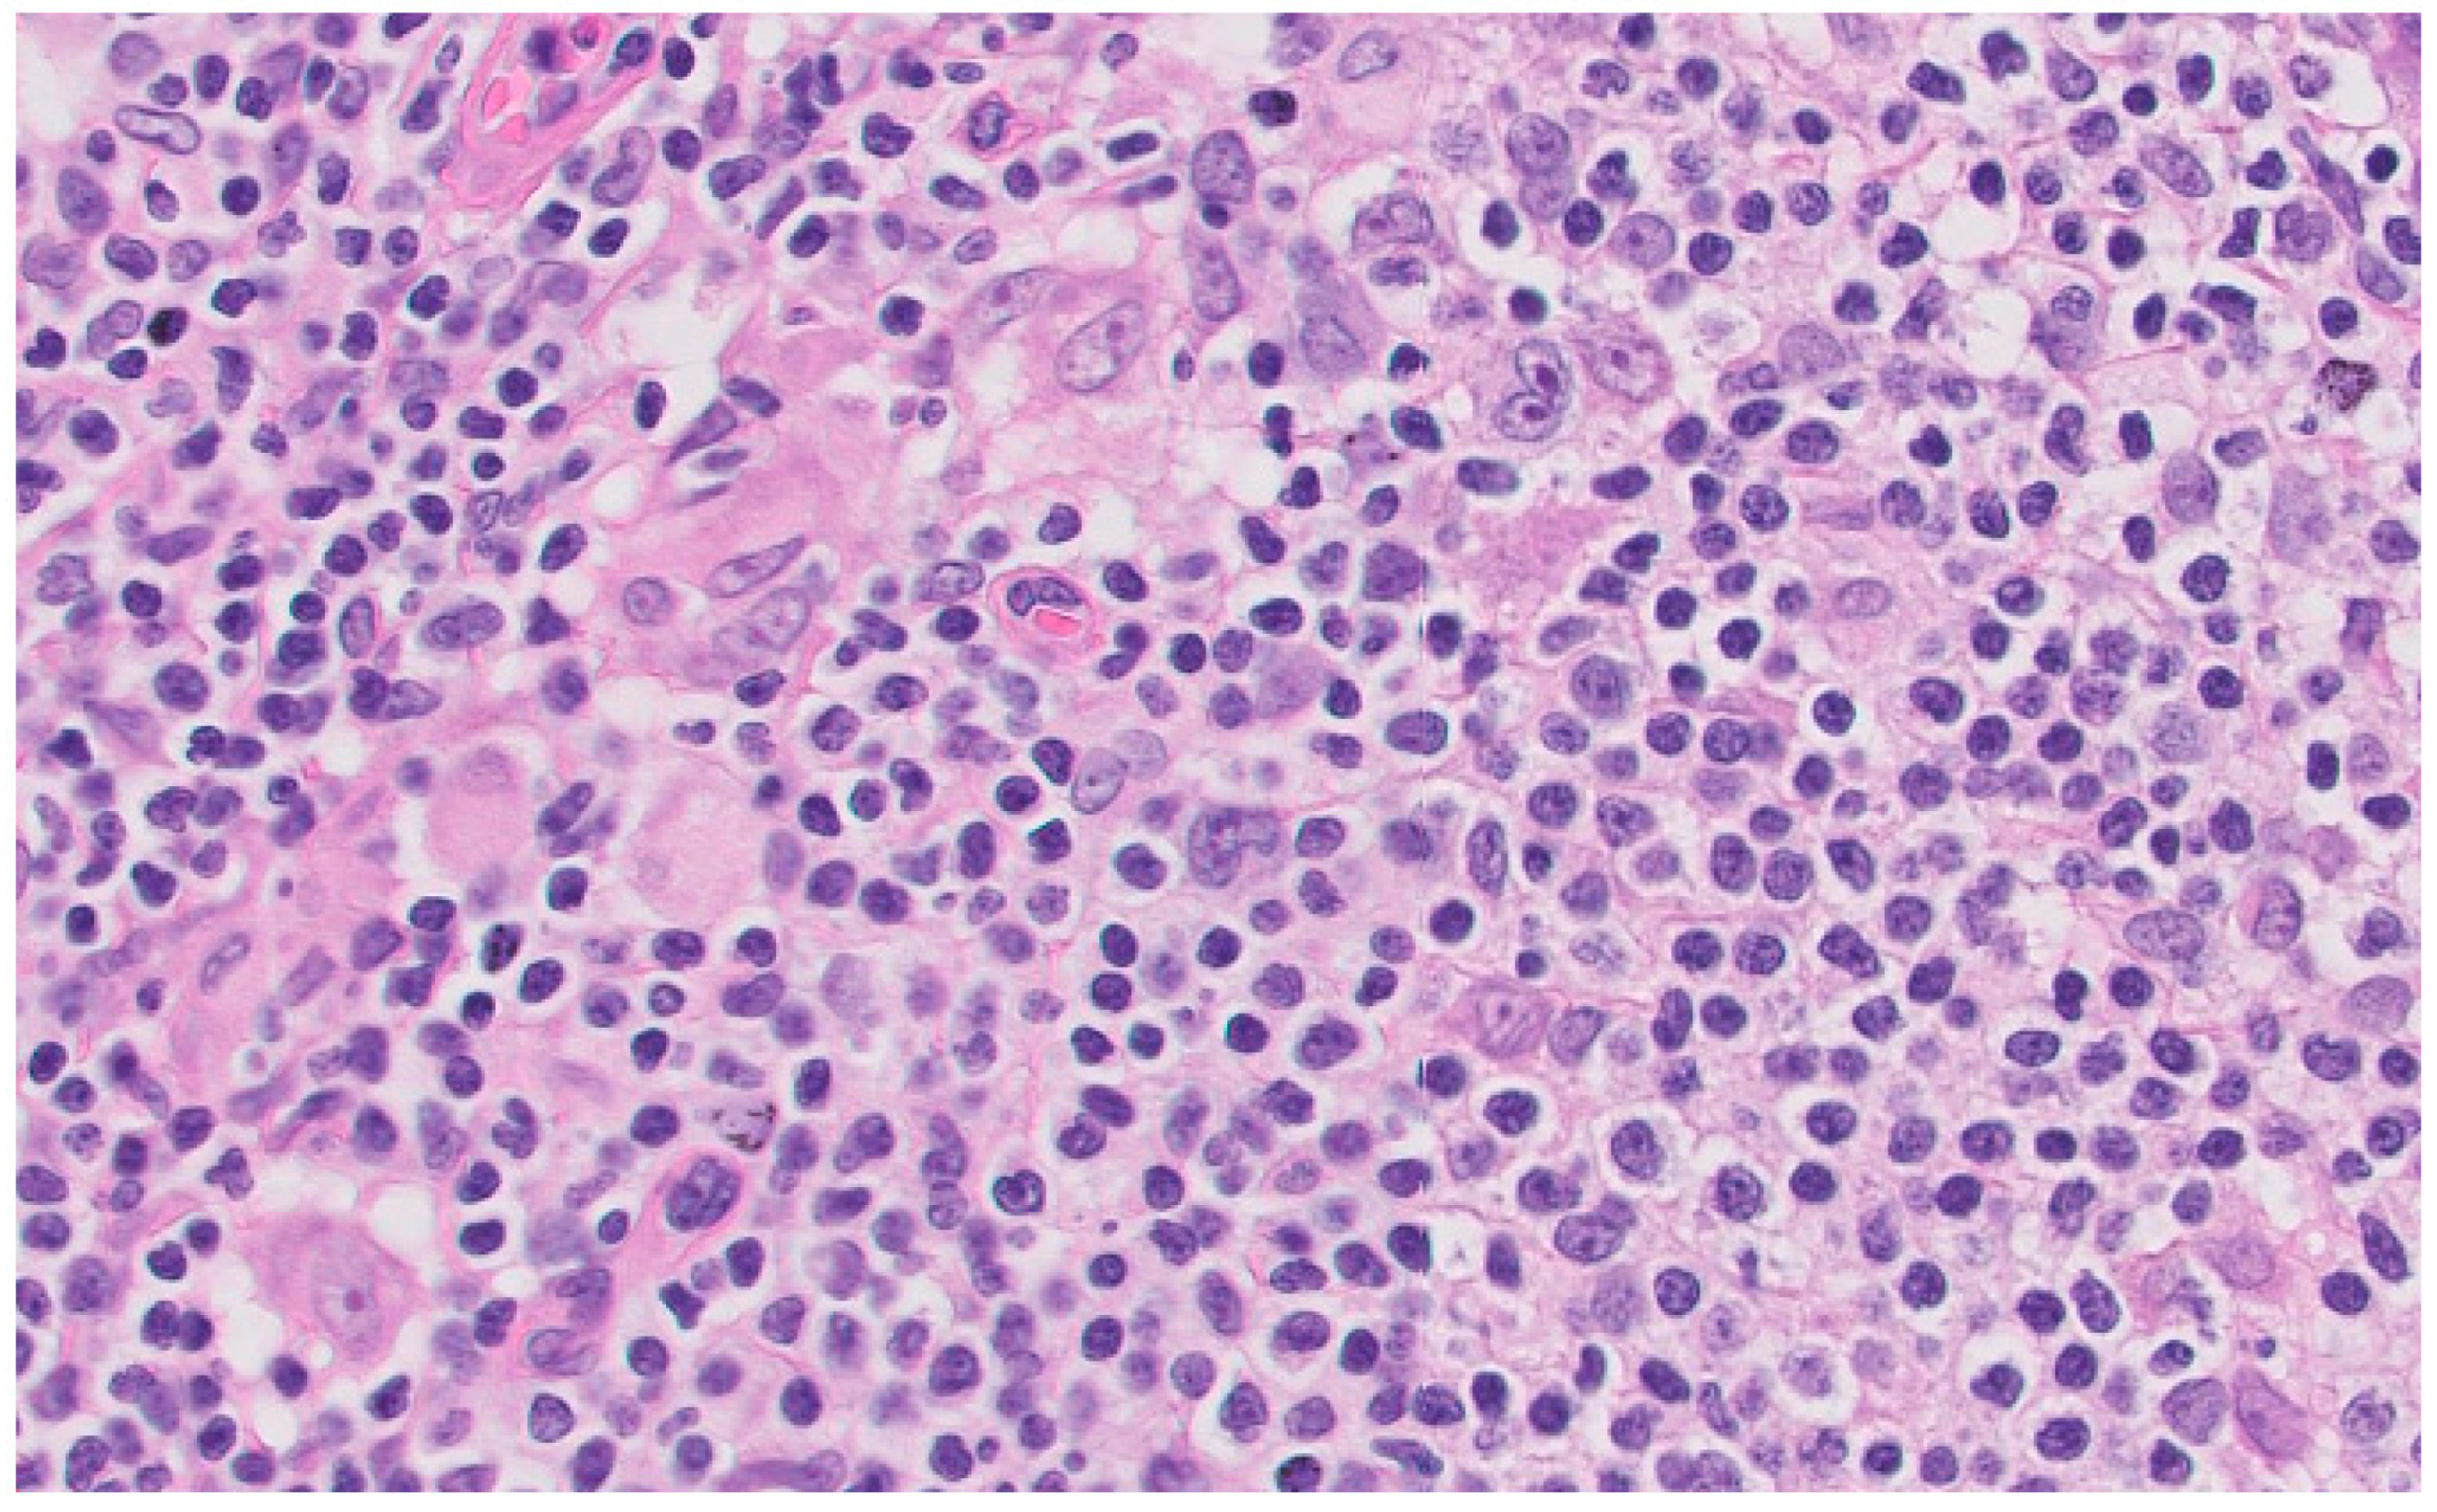

A lymph node biopsy was performed showing hyperplasia of germinal centers with increased vascularization in the centers and interfollicular area with expansion and fibrosis of the capsule. Monocytic cells were revealed in subcapsular sinusoids, histiocyte clusters, and numerous plasma cells in the centers and perifollicular area that did not show light chain restriction. Abundant CD30 cells were revealed in the centers and interfollicular area with numerous EBV (EBER)-positive cells in the centers, although in smaller numbers, surrounding them. These findings were compatible with the histologic diagnosis of HIV-related lymphoid hyperplasia associated with possible EBV reactivation (Figure 3).

Figure 3. Inguinal lymph node biopsy. Hematoxylin eosin stain × 40.